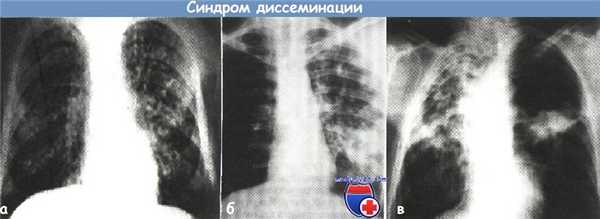

а - синдром выраженной гематогенной диссеминации очагов при диссеминированном туберкулезе легких (рентгенограмма органов грудной клетки в прямой проекции)

б - синдром лимфогенной диссеминации очагов в верхней доле правого легкого (рентгенограмма органов грудной клетки в прямой проекции).

в - синдром бронхогенной диссеминации в правое легкое при фиброзно-кавернозном туберкулезе (рентгенограмма органов грудной клетки в прямой проекции).